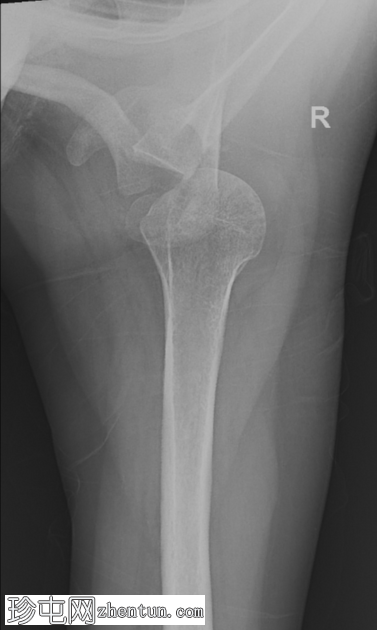

正位片

前后位片

肱骨头显示部分内旋。肩关节正常匹配度丧失。此位片未见明显相关骨折。